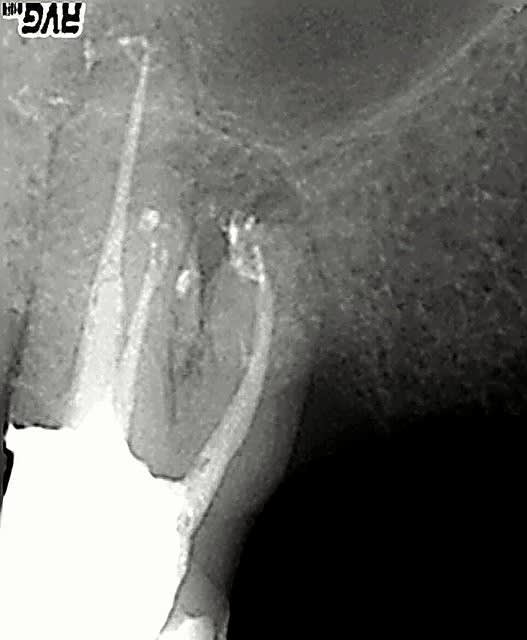

21/12/2006 à 18h39

c'est un faux canal? bin zut alors!!

y avait un trou, y avait une butée apicale.

aucune dispersion de gutta et de ciment.

aucune suite post-op.

ça doit être un faux canal.

Autour d'un canal,ne doit on pas voir l'image de la racine? c'est la moindre des choses quand même